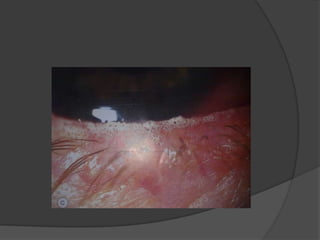

 Cornea-

a. Punctate epithelial erosions in the interpalpebral

and inferior cornea.

b. Mucus filaments- stain with rose bengal

c. Mucus plaques- composed of mucus, epithelial

cells, proteinaceous and lipoidal material.